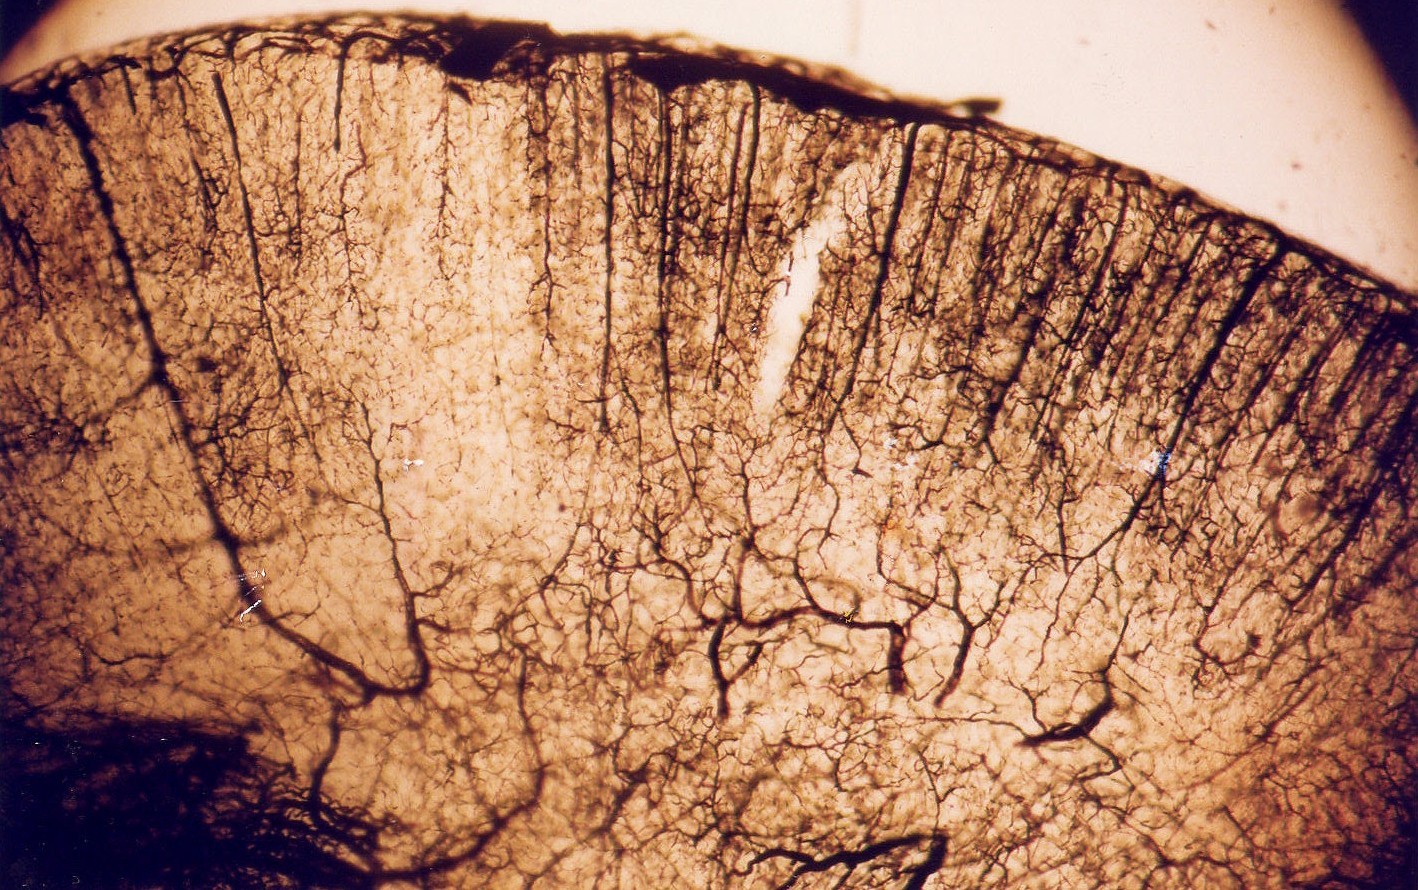

In the acupuncture group, a small white area persisted in the subcortex, indicating that the treatment's neuroprotective effect did not fully reach this region. This limitation is likely due to the inherently lower baseline blood circulation in the subcortical area compared to the cortex. The cerebral perfusion image below, taken under microscopy, illustrates this fundamental difference in vascular supply between the two regions.